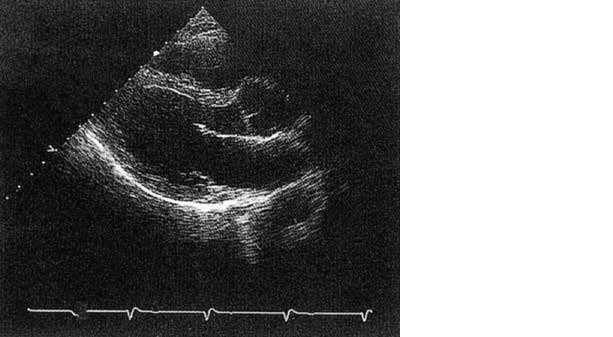

心臓超音波像を示す。正しいのはどれか。

• 1. 心尖部長軸断層像である。

• 2. Mモードである。

• 3. 大動脈は描出されていない。

• 4. 右房が描出されている。

• 5. 心室拡張期である。